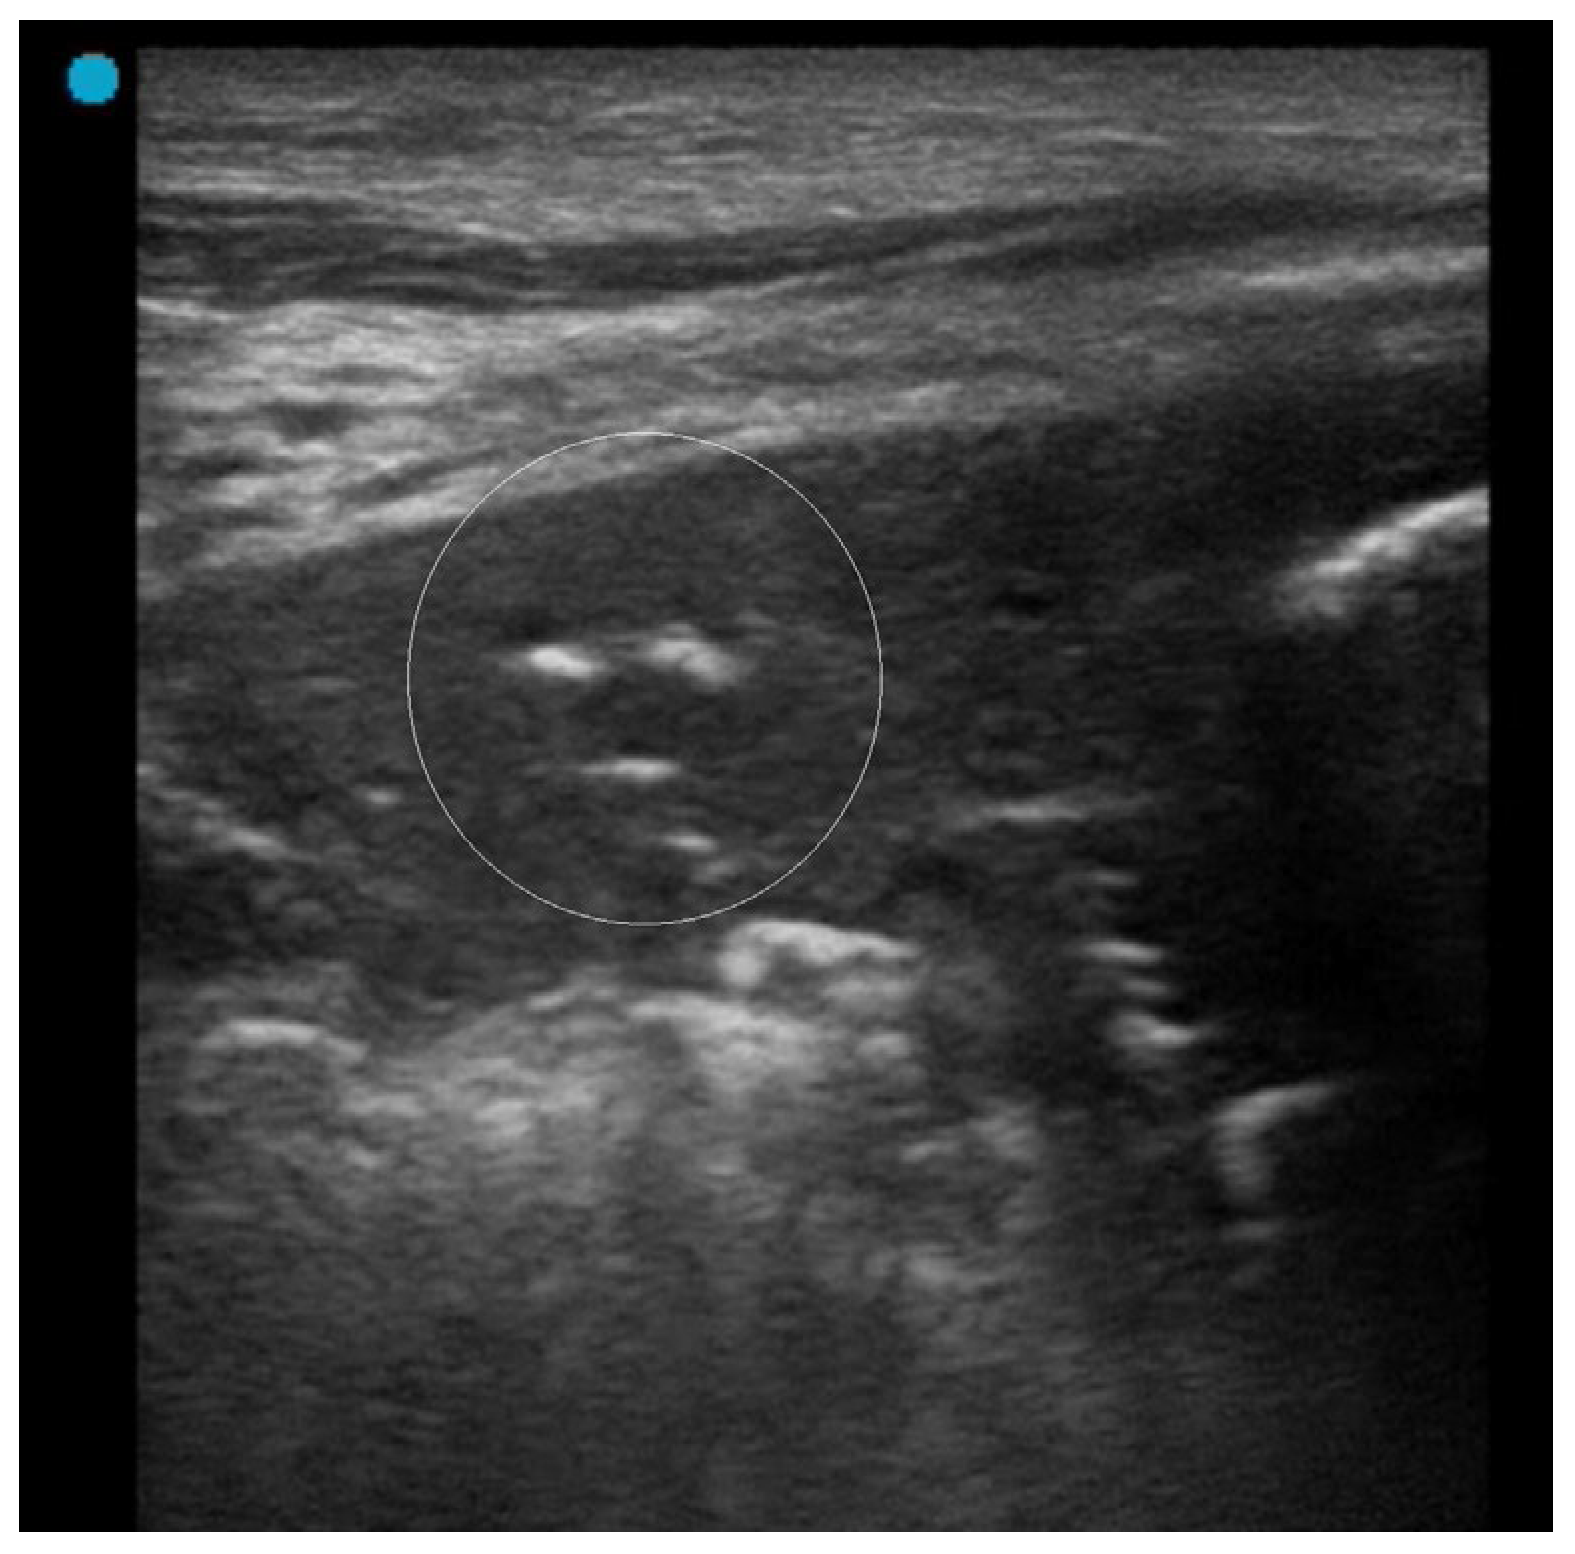

- Yoon, H.; Kim, S.J.; Kim, K.; Lee, J.E.; Jhun, B.W. The utility of thoracic ultrasound in patients with acute eosinophilic pneumonia. PLoS ONE 2015, 10, e0124370. [Google Scholar] [CrossRef]

- Sperandeo, M.; Rea, G.; Grimaldi, M.A.; Trovato, F.; Dimitri, L.M.; Carnevale, V. Contrast-enhanced ultrasound does not discriminate between community acquired pneumonia and lung cancer. Thorax 2017, 72, 178–180. [Google Scholar] [CrossRef] [PubMed]

- Kuo, Y.W.; Chen, Y.L.; Wu, H.D.; Chien, Y.C.; Huang, C.K.; Wang, H.C. Application of transthoracic shear-wave ultrasound elastography in lung lesions. Eur. Respir. J. 2021, 57, 2002347. [Google Scholar] [CrossRef]

- Quarato, C.M.I.; Venuti, M.; Dimitri, L.; Lacedonia, D.; Simeone, A.; Mirijello, A.; De Cosmo, S.; Maiello, E.; Taurchini, M.; Scioscia, G.; et al. Transthoracic ultrasound shear wave elastography for the study of subpleural lung lesions. Ultrasonography 2022, 41, 93–105. [Google Scholar] [CrossRef]